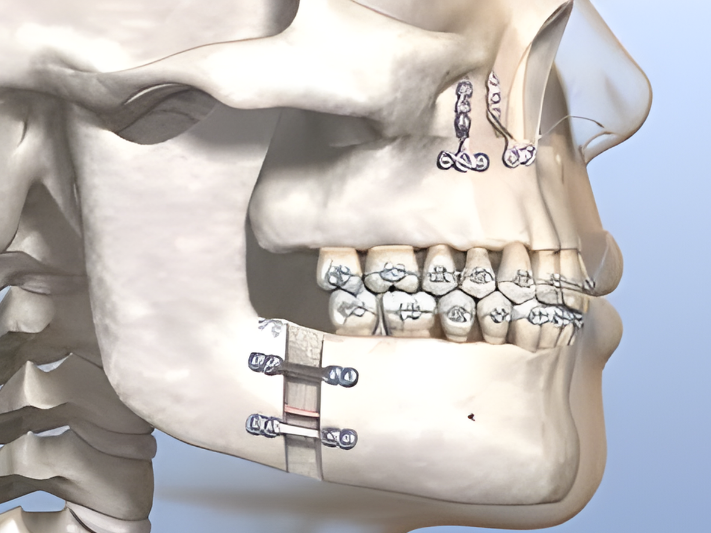

Jaw Surgery

Correct jaw irregularities with maxillofacial and orthognathic procedures for improved function and appearance.